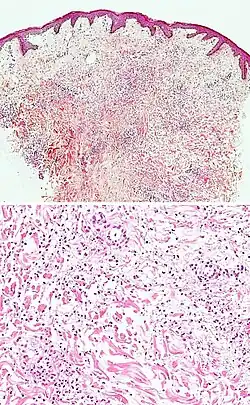

Kaposi’s sarcoma in patch stage The patch stage typically shows irregular proliferation of jagged vascular channels in the dermis below an integral epidermis. The so-called promontory sign is sometimes found in patch stage lesions and denotes vascular spaces surrounding pre-existing blood (see image).[23]

vessels